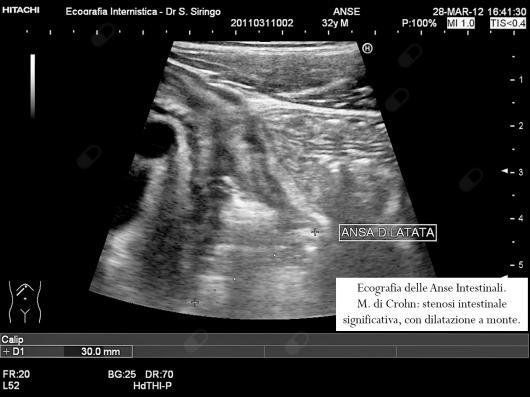

E’ una metodica di primo livello da impiegare nello studio dei disturbi addominali. In particolare, insieme ad alcuni specifici esami di laboratorio, permette un’agevole diagnosi differenziale tra colon irritabile e malattie infiammatorie dell’intestino quali la m. di Crohn e la colite ulcerosa. Inoltre, nel sospetto di m. di Crohn, consente di orientare rapidamente la diagnosi permettendo di rilevare l’ispessimento delle pareti del piccolo intestino e del colon che contraddistingue questa malattia.

Nella m. di Crohn, dopo la diagnosi, è un utilissimo mezzo per seguirne l’evoluzione, la risposta alla terapia e rilevare le possibili complicazioni quali ascessi o restringimenti dell’intestino.